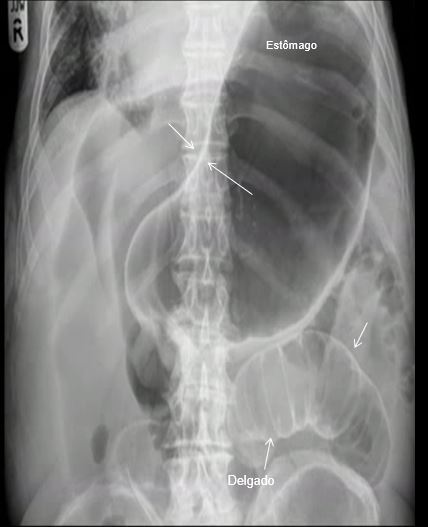

NOME DO EXAME? INCIDÊNCIA? IDENTIFIQUE:

É ADULTO?

RD SIMPLES DO ABDOME EM DECÚBITO DORSAL.

1- FÍGADO SETA VERMELHA – BORDA HEPÁTICA

2- BAÇO SETA AZUL – 12º ARCO COSTAL D

SETAS AMARELAS – FEZES NO CÓLON ASCENDENTE E RETO E SIGMÓIDE ( MICROBOLHAS GASOSAS)

SETA ROXA- ARTICULAÇÃO SACRO-ILÍACA D

SETA VERDE- ARTICULAÇÃO COXO-FEMORAL DIREITA.

TRATA-SE DE UM ADOLESCENTE PORQUE AS LINHAS DE CRESCIMENTO (SETAS LARANJAS ) SÃO VISÍVEIS.